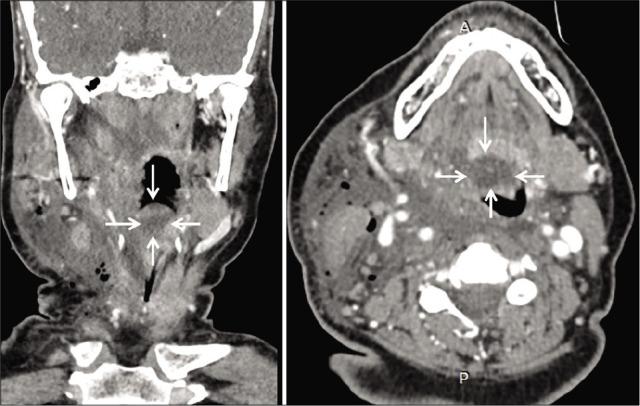

A 60-year-old female with degenerative cervical myelopathy and a previously undiagnosed epiglottic cyst underwent a C5-C6 ACDF; notably, the anesthesiologist found an epiglottic cyst when the patient was first intubated. Two hours postoperatively, the patient acutely developed severe neck swelling with airway obstruction due to angioedema. She was immediately treated with hydrocortisone and required a tracheostomy. The edema decreased markedly in the next 12 h and by the 3 postoperative day it resolved. Three months later, she had no residual medical sequelae.

一名60岁患有退行性颈椎病且此前未诊断出会厌囊肿的女性接受了C5 - C6节段的ACDF手术;值得注意的是,麻醉医生在患者首次插管时发现了会厌囊肿。术后两小时,患者因血管性水肿急性出现严重颈部肿胀并伴有气道梗阻。她立即接受了氢化可的松治疗,并需要进行气管切开术。水肿在接下来的12小时内明显减轻,术后第3天消退。三个月后,她没有残留的医学后遗症。